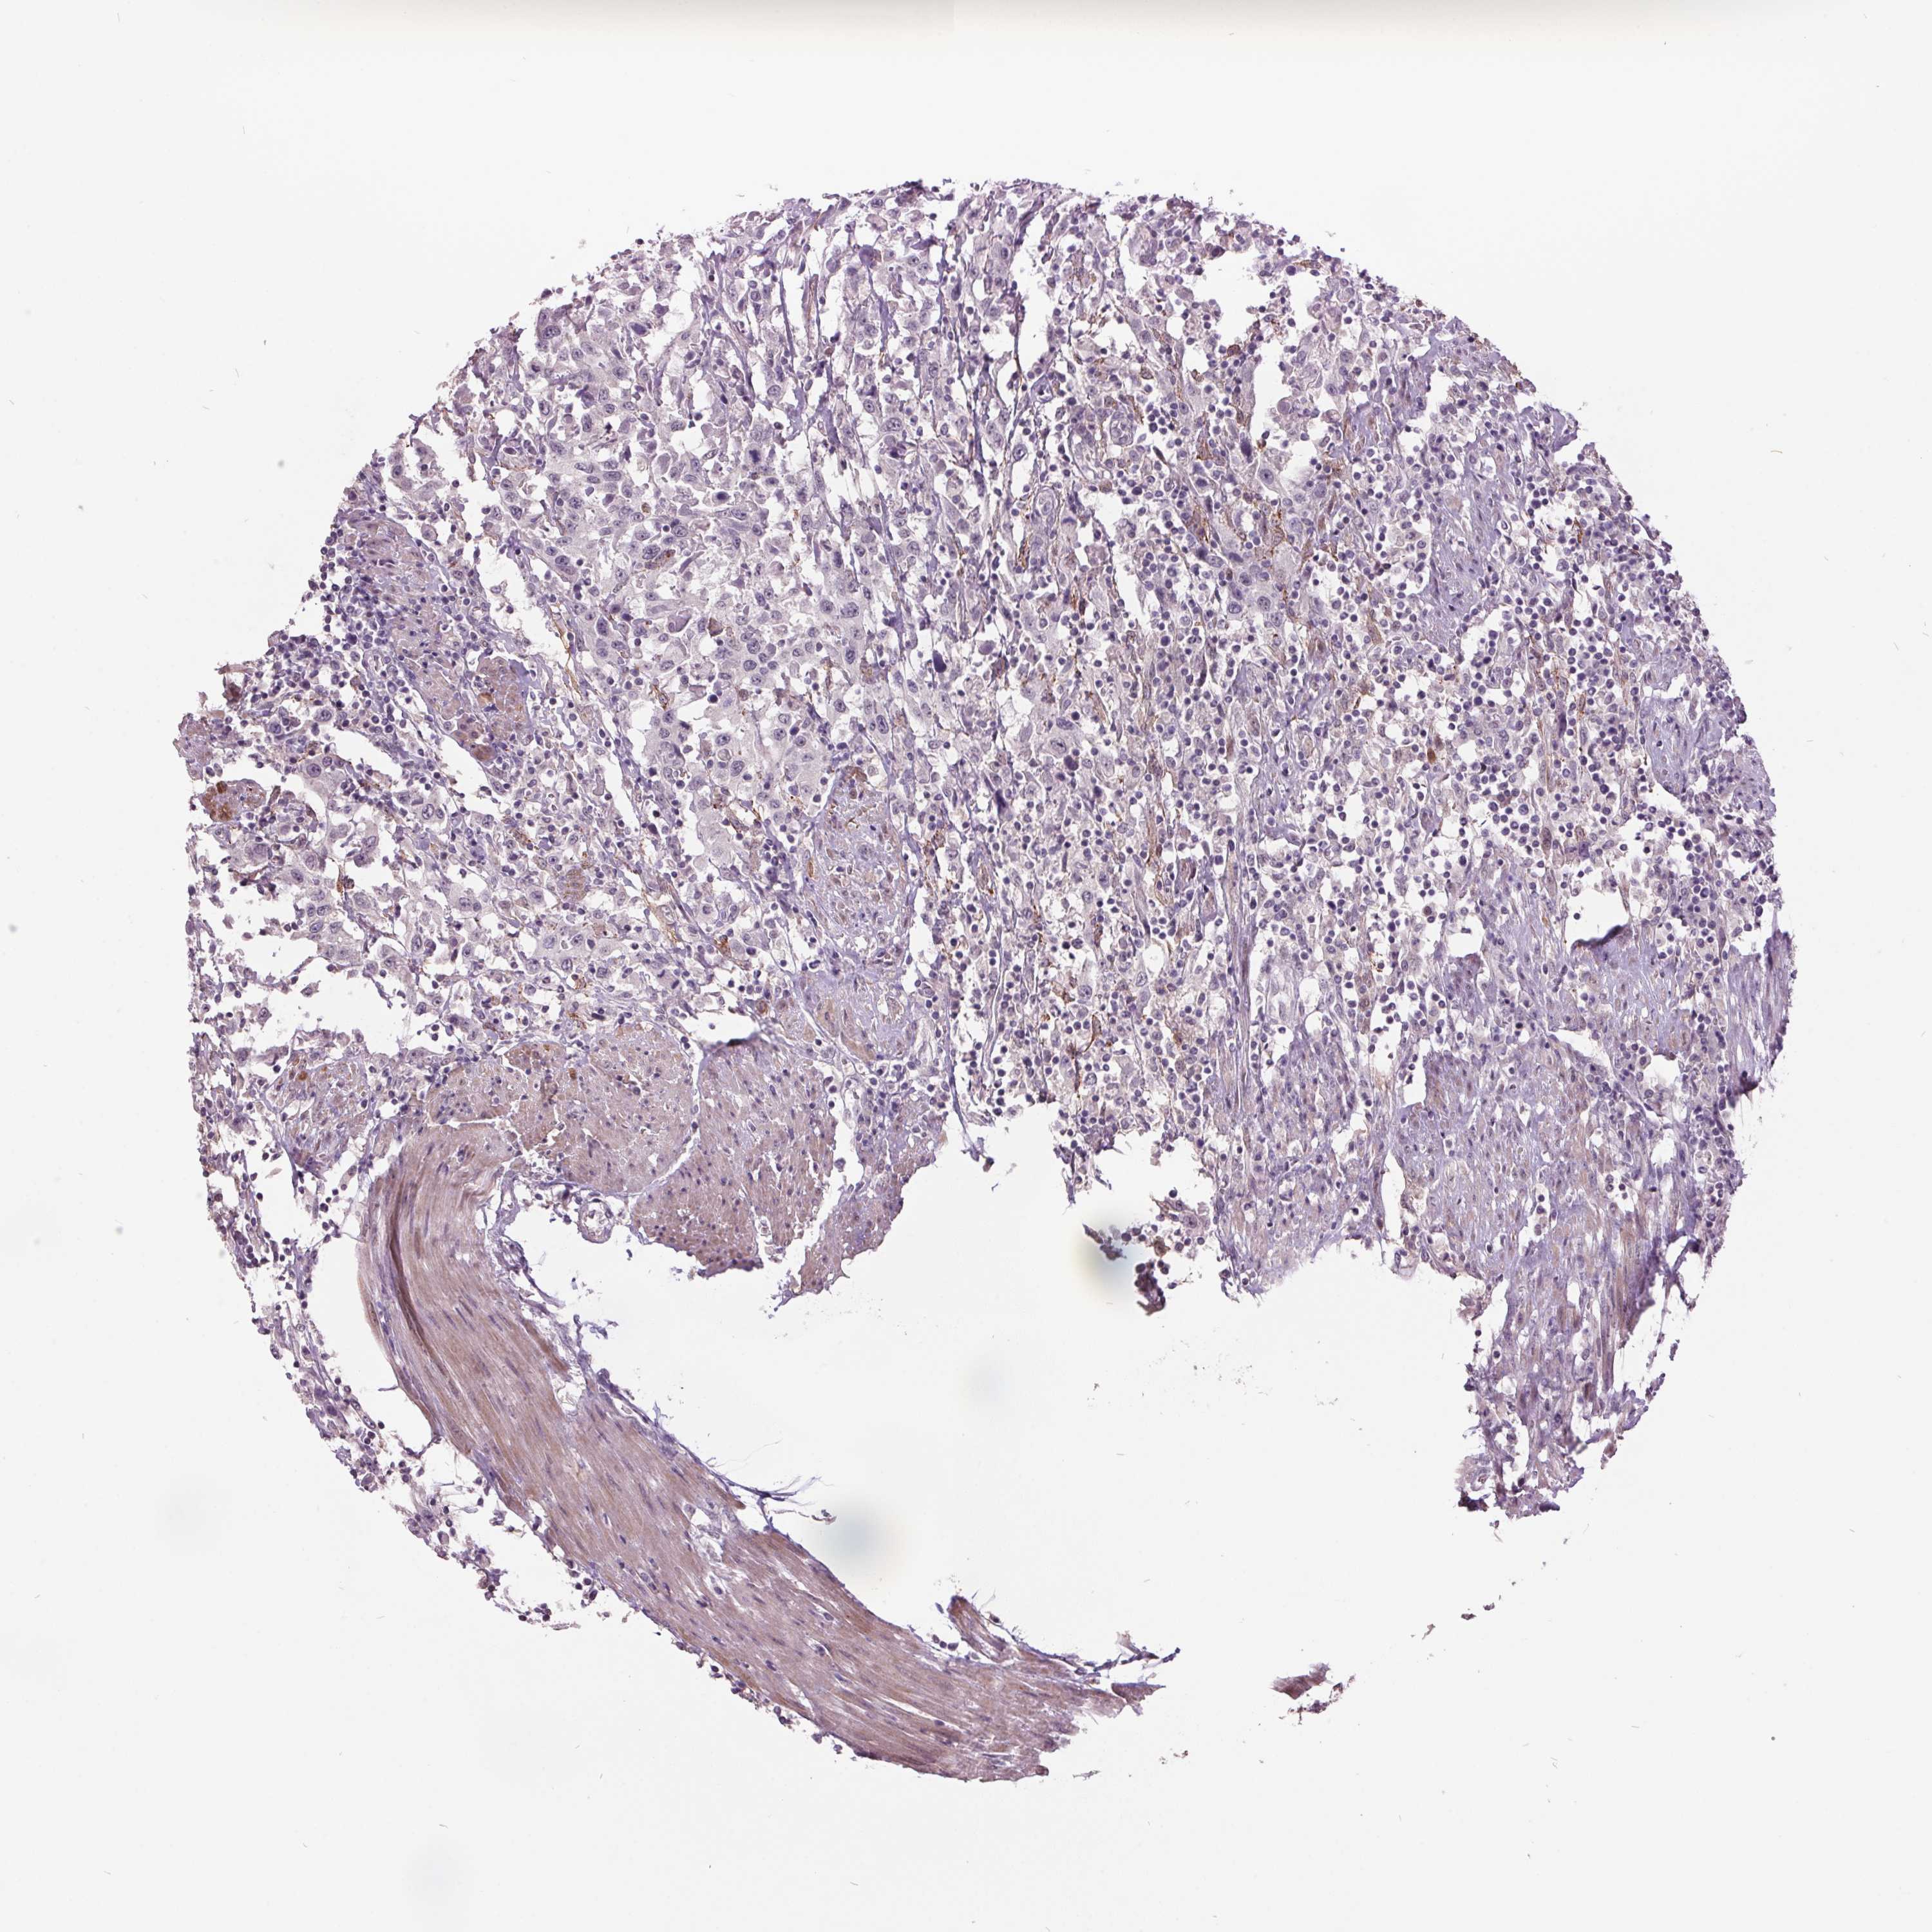

UROTHELIAL CANCER - Protein expressioni

A mouse-over function shows sample information and annotation data. Click on an image to view it in a full screen mode. Samples can be filtered based on level of antibody staining by selecting one or several of the following categories: high, medium, low and not detected. The assay and annotation is described here.

Note that samples used for immunohistochemistry by the Human Protein Atlas do not correspond to samples in the TCGA dataset.

Antibody stainingi

Antibody staining in the annotated cell types in the current human tissue is reported as not detected, low, medium, or high, based on conventional immunohistochemistry profiling in selected tissues. This score is based on the combination of the staining intensity and fraction of stained cells.

Each image is clickable and will lead to virtual microscopy that enables deeper exploration of all samples and also displays staining intensity scores, fraction scores and subcellular localization as well as patient and tissue information for each sample.

Antibody HPA052136

Antibody HPA056962

Staining

High

Medium

Low

Not detected

Intensity

Strong

Moderate

Weak

Negative

Quantity

>75%

75%-25%

<25%

None

Location

Nuclear

Cytoplasmic/membranous

Cytoplasmic/membranous,nuclear

Urothelial carcinoma, High grade

Urothelial carcinoma, Low grade

Urothelial carcinoma, NOS